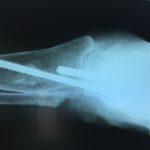

RTG po operacji